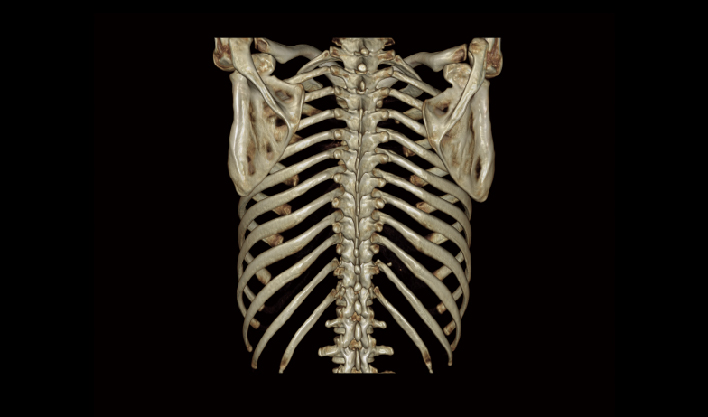

El detector de área amplia, combinado con la rotación de alta velocidad, garantiza imágenes de alta resolución y minimiza los artefactos de movimiento.

El detector de cuerpo ancho de cuarta generación, de desarrollo propio, cubre más áreas de tejido.